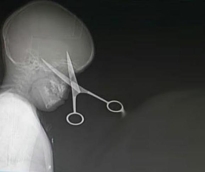

تمكن فريق طبي في جدة من إنقاذ حياة طفل سعودي، وذلك باستخراج مقص اخترق جمجمته واستقر داخل الفص الأمامي للمخ. وأجرى فريق طبي متخصص في المخ والأعصاب بمستشفى الملك فهد العام بجدة، عملية ناجحة لاستخراج المقص دون أية مضاعفات، وذلك بعمل فتحة من وراء الشعر حتى يتم المحافظة على الشكل الجمالي للرأس بعد العملية. وتعتبر الجراحة من العمليات المعقدة جداً، نظراً لحساسية المنطقة التي أجريت فيها العملية وهي منطقة المخ، واستغرقت العملية 3 ساعات، وذلك حسبما أوضح المكتب الإعلامي بالمستشفى. وأكد المكتب الإعلامي بالمستشفى، أن المريض حالياً، بحالة صحية جيدة، حيث خضع لأشعة مقطعية للتأكد من نجاح العملية.